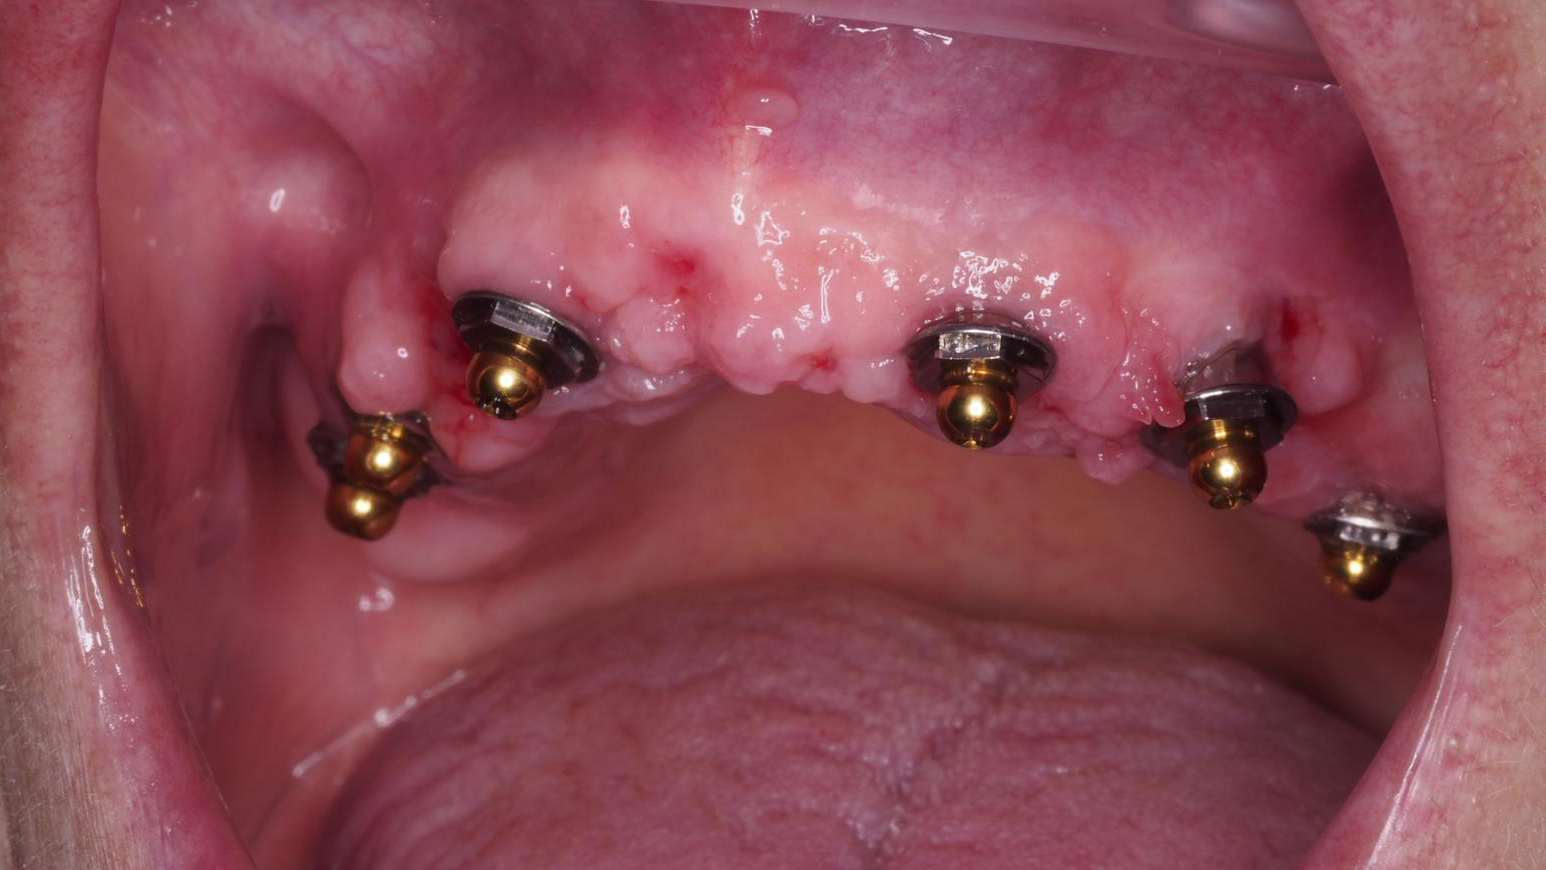

La rehabilitación oral completa en pacientes parcialmente edéntulos requiere una planificación cuidadosa, que integre tanto la función como la estética. La aplicación de técnicas mínimamente invasivas asociadas a protocolos de carga inmediata optimiza la experiencia del paciente, disminuye los tiempos clínicos y facilita la recuperación de la función oral, con resultados estables y predecibles.

En el caso presentado, la utilización de implantes monobloque Easy-Link en el maxilar superior, combinados con implantes convencionales atornillados en el maxilar inferior, permitió alcanzar una rehabilitación integral ajustada a la anatomía y a las necesidades específicas de la paciente.